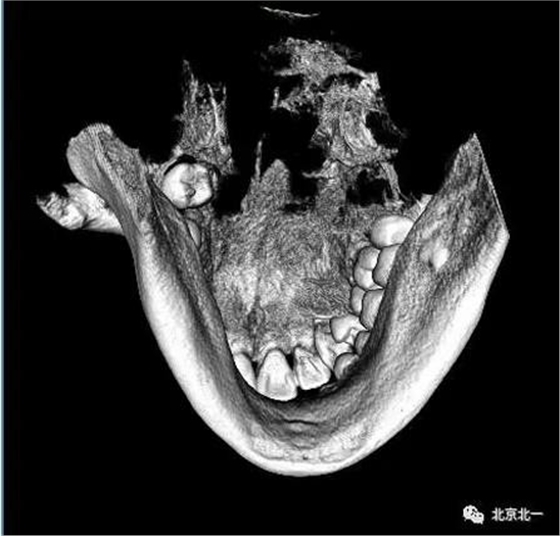

圖五:三維重建可見牙冠突破舌側(cè)